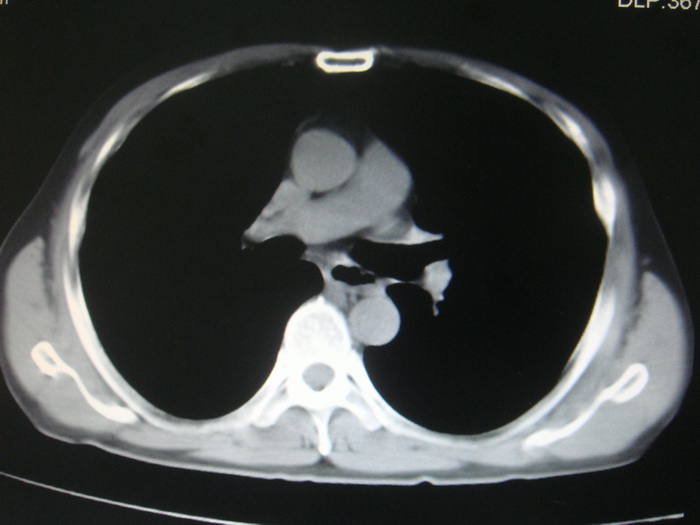

标题: CT28366:男性,45岁,偶尔发现右颈部肿块行胸部CT扫描。 [打印本页]

男性,45岁,偶尔发现右颈部肿块行胸部ct扫描。

两肺多发结节灶及纵膈淋巴结肿大考虑为转移

两肺多发性转移瘤,纵隔淋巴结转移。

两肺多发性转移瘤,纵隔淋巴结转移。食道中上段管壁似乎增厚,作相关检查。

两肺多发性转移瘤,前上纵隔淋巴结转移。